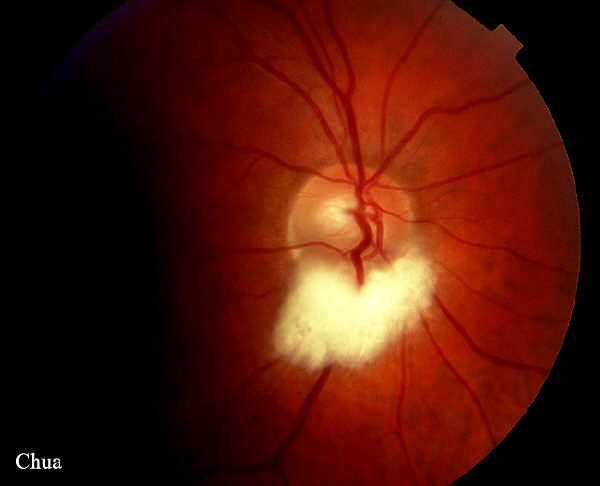

| History: An incidental finding of a patient with

bilateral myelinated nerve fibres. The myelination appears

white with feathery edges. Normally, myelination of the optic nerve stops at lamina cribosa but in some normal people it can extend onto the retina. Myelination if present often occurs around the optic disc but may be found anywhere on the retina. Visual fields in this patient will be expected to show increased blind spots as the myelination prevents light falling on the photoreceptors. |